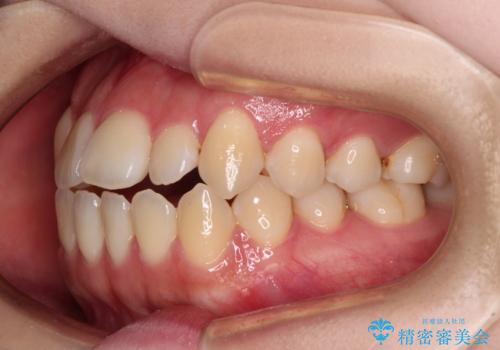

舌突出癖による開咬 舌のトレーニングを行いながら前歯の隙間を改善

- 上下前歯の隙間を気にして来院された患者様です。

前歯が、舌の突出癖により上下前歯が非接触となっている状態でした。

ワイヤー矯正での開咬改善には時間がかかります。

舌の突出癖改善のトレーニングをしっかりと行っていただき、上下前歯が接触する咬み合わせを達成することができました。